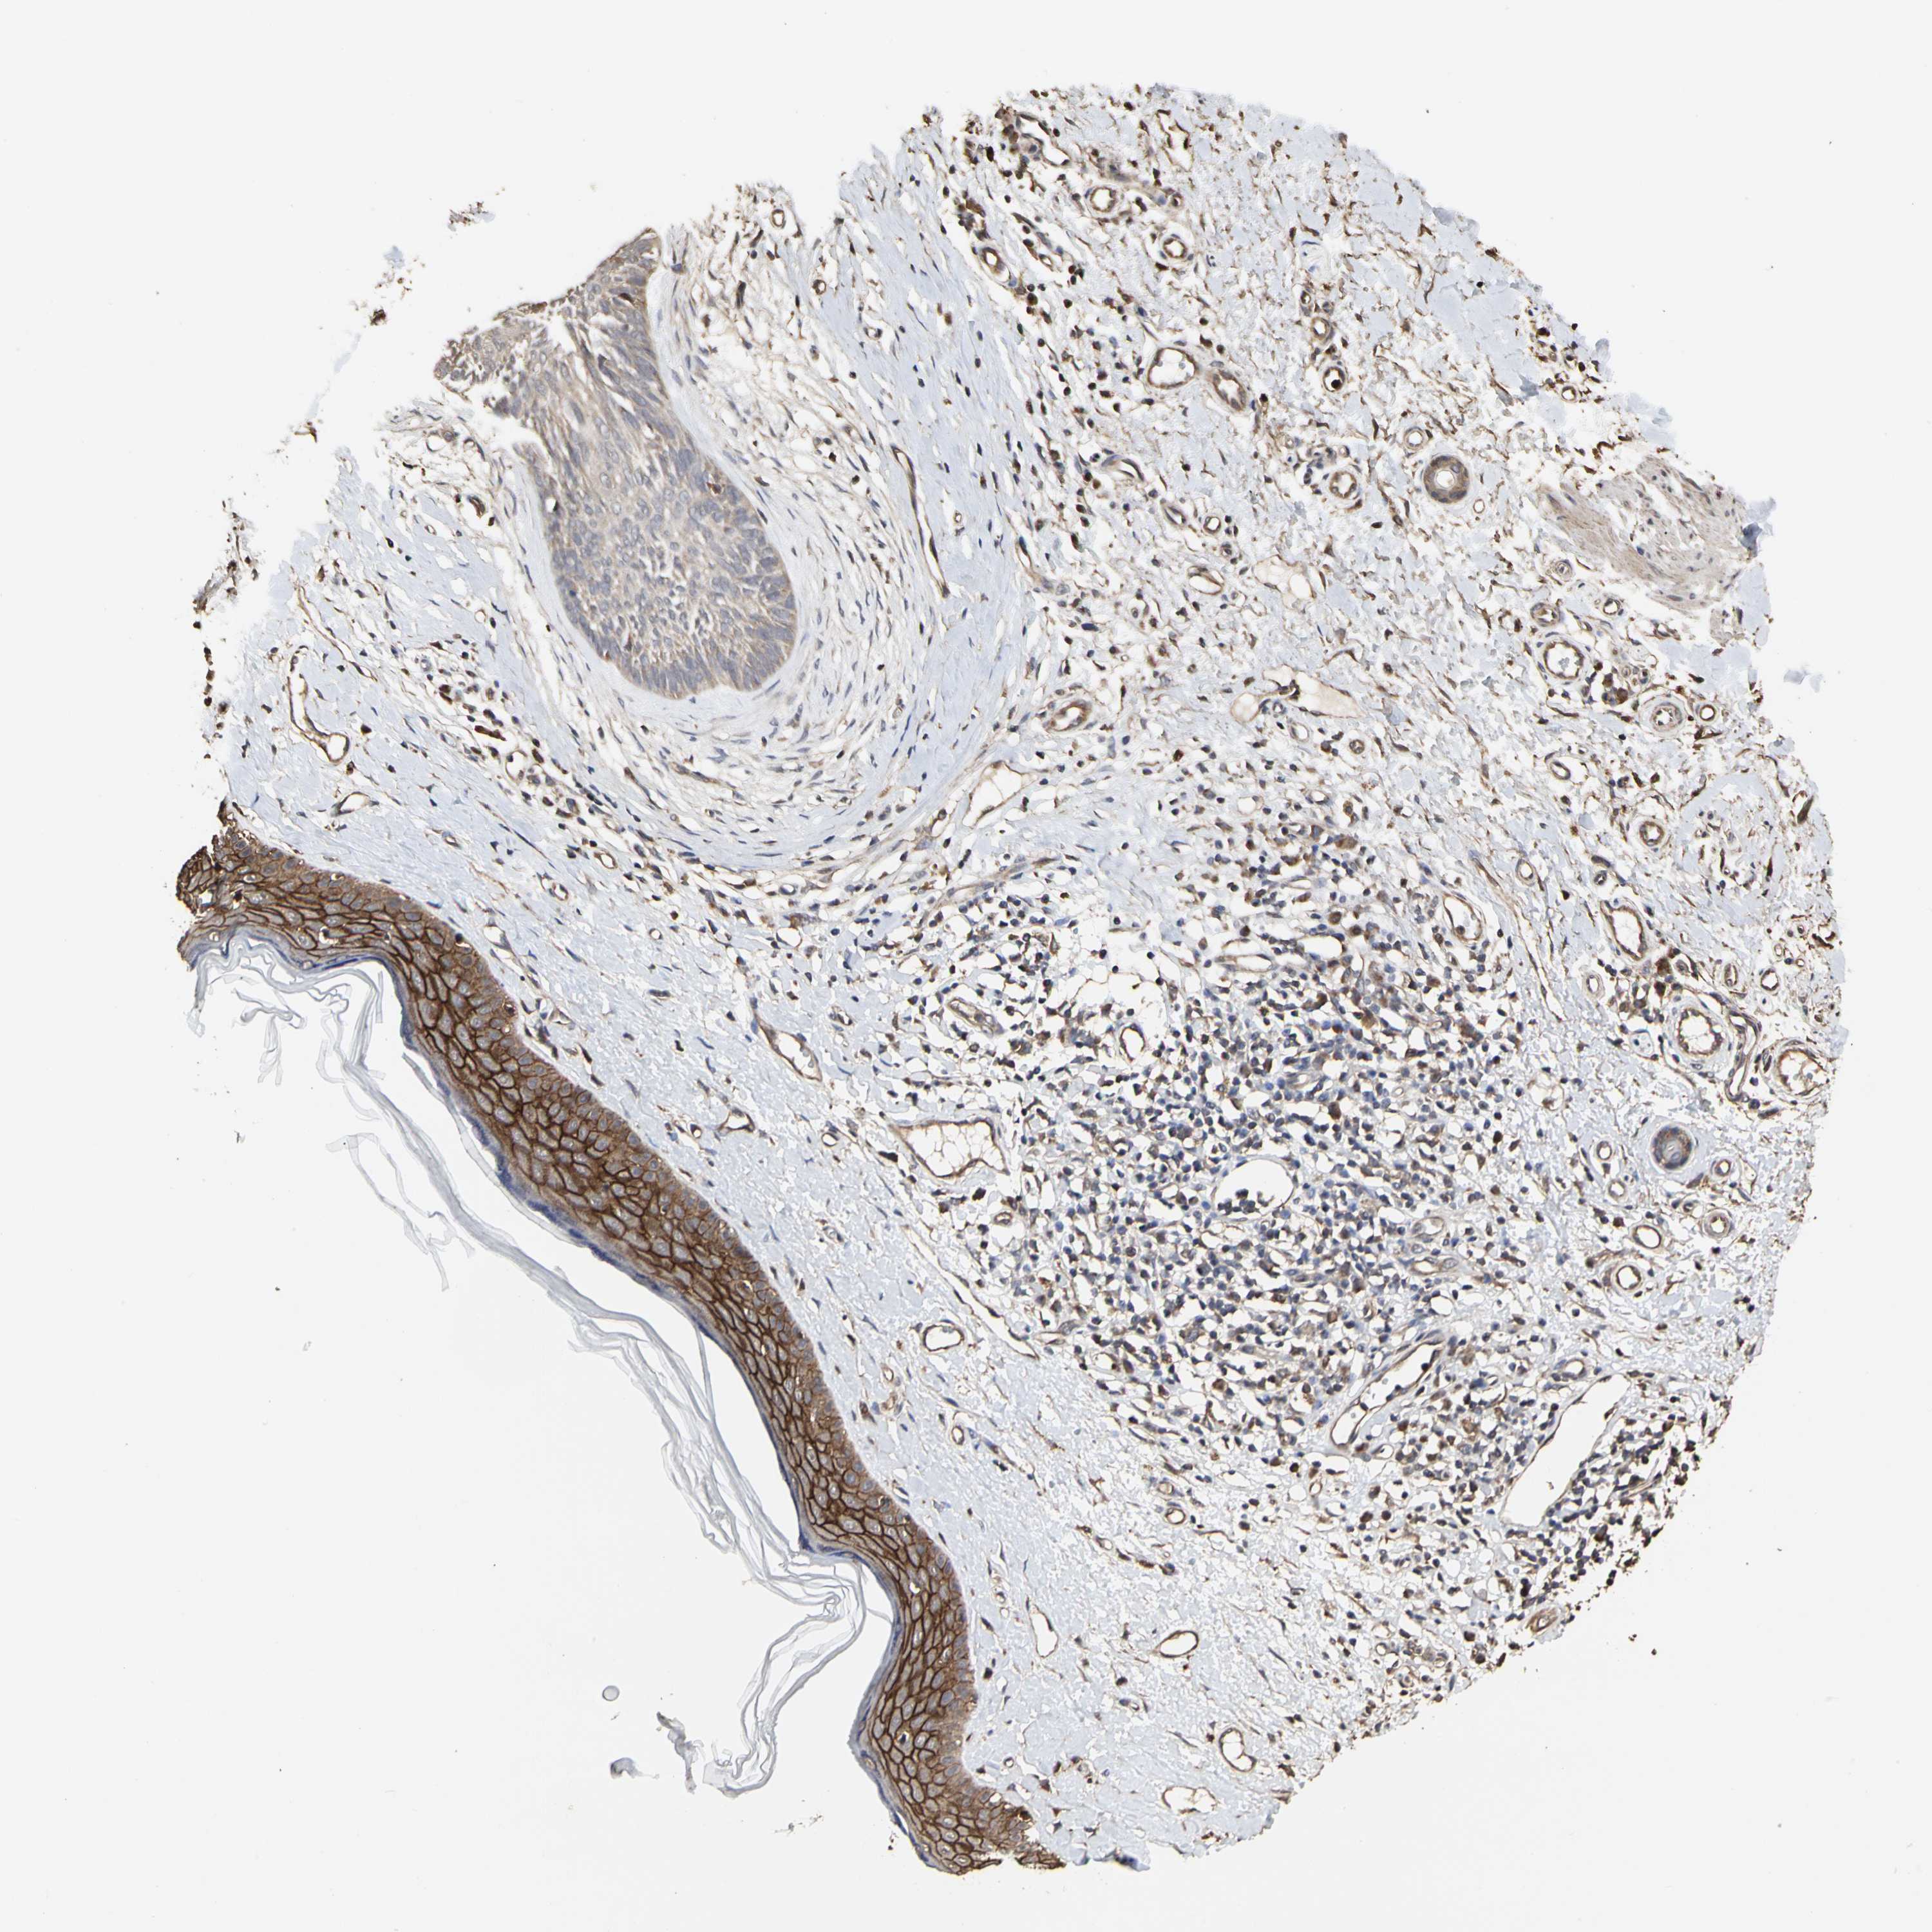

• TAOK1

CANCER SKIN CANCER Show tissue menu

Basal cell and squamous cell cancer

Human cancer

SKIN CANCER - Protein expressioni

A mouse-over function shows sample information and annotation data. Click on an image to view it in a full screen mode. Samples can be filtered based on level of antibody staining by selecting one or several of the following categories: high, medium, low and not detected. The assay and annotation is described here.

Antibody stainingi

Antibody staining in the annotated cell types in the current human tissue is reported as not detected, low, medium, or high, based on conventional immunohistochemistry profiling in selected tissues. This score is based on the combination of the staining intensity and fraction of stained cells.

Each image is clickable and will lead to virtual microscopy that enables deeper exploration of all samples and also displays staining intensity scores, fraction scores and subcellular localization as well as patient and tissue information for each sample.

Antibody HPA007669

Staining

High

Medium

Low

Not detected

Intensity

Strong

Moderate

Weak

Negative

Quantity

>75%

75%-25%

<25%

None

Location

Nuclear

Cytoplasmic/membranous

Cytoplasmic/membranous,nuclear

Squamous cell carcinoma, NOS

Basal cell carcinoma